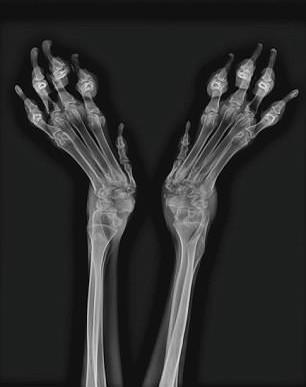

Το σκυλάκι επί μήνες βρισκόταν κλειδωμένο μέσα σε ένα μικρό κλουβί με αποτέλεσμα να παραμορφωθούν τα άκτα του.

Εξαιτίας του εγκλεισμού σε κλουβί, όχι μόνο παραμορφώθηκαν τα πόδια του αλλά και οι μυς του σκύλου έχουν ατροφήσει, δυσκολεύοντας περαιτέρω το έργο των κτηνιάτρων.